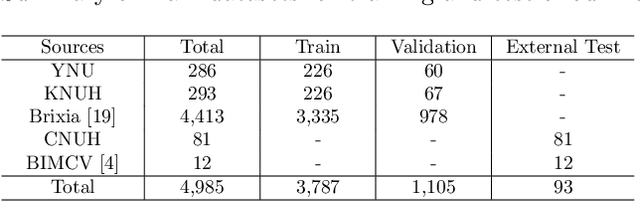

Abstract:Developing a robust algorithm to diagnose and quantify the severity of COVID-19 using Chest X-ray (CXR) requires a large number of well-curated COVID-19 datasets, which is difficult to collect under the global COVID-19 pandemic. On the other hand, CXR data with other findings are abundant. This situation is ideally suited for the Vision Transformer (ViT) architecture, where a lot of unlabeled data can be used through structural modeling by the self-attention mechanism. However, the use of existing ViT is not optimal, since feature embedding through direct patch flattening or ResNet backbone in the standard ViT is not intended for CXR. To address this problem, here we propose a novel Vision Transformer that utilizes low-level CXR feature corpus obtained from a backbone network that extracts common CXR findings. Specifically, the backbone network is first trained with large public datasets to detect common abnormal findings such as consolidation, opacity, edema, etc. Then, the embedded features from the backbone network are used as corpora for a Transformer model for the diagnosis and the severity quantification of COVID-19. We evaluate our model on various external test datasets from totally different institutions to evaluate the generalization capability. The experimental results confirm that our model can achieve the state-of-the-art performance in both diagnosis and severity quantification tasks with superior generalization capability, which are sine qua non of widespread deployment.

Abstract:Under the global pandemic of COVID-19, building an automated framework that quantifies the severity of COVID-19 and localizes the relevant lesion on chest X-ray images has become increasingly important. Although pixel-level lesion severity labels, e.g. lesion segmentation, can be the most excellent target to build a robust model, collecting enough data with such labels is difficult due to time and labor-intensive annotation tasks. Instead, array-based severity labeling that assigns integer scores on six subdivisions of lungs can be an alternative choice enabling the quick labeling. Several groups proposed deep learning algorithms that quantify the severity of COVID-19 using the array-based COVID-19 labels and localize the lesions with explainability maps. To further improve the accuracy and interpretability, here we propose a novel Vision Transformer tailored for both quantification of the severity and clinically applicable localization of the COVID-19 related lesions. Our model is trained in a weakly-supervised manner to generate the full probability maps from weak array-based labels. Furthermore, a novel progressive self-training method enables us to build a model with a small labeled dataset. The quantitative and qualitative analysis on the external testset demonstrates that our method shows comparable performance with radiologists for both tasks with stability in a real-world application.